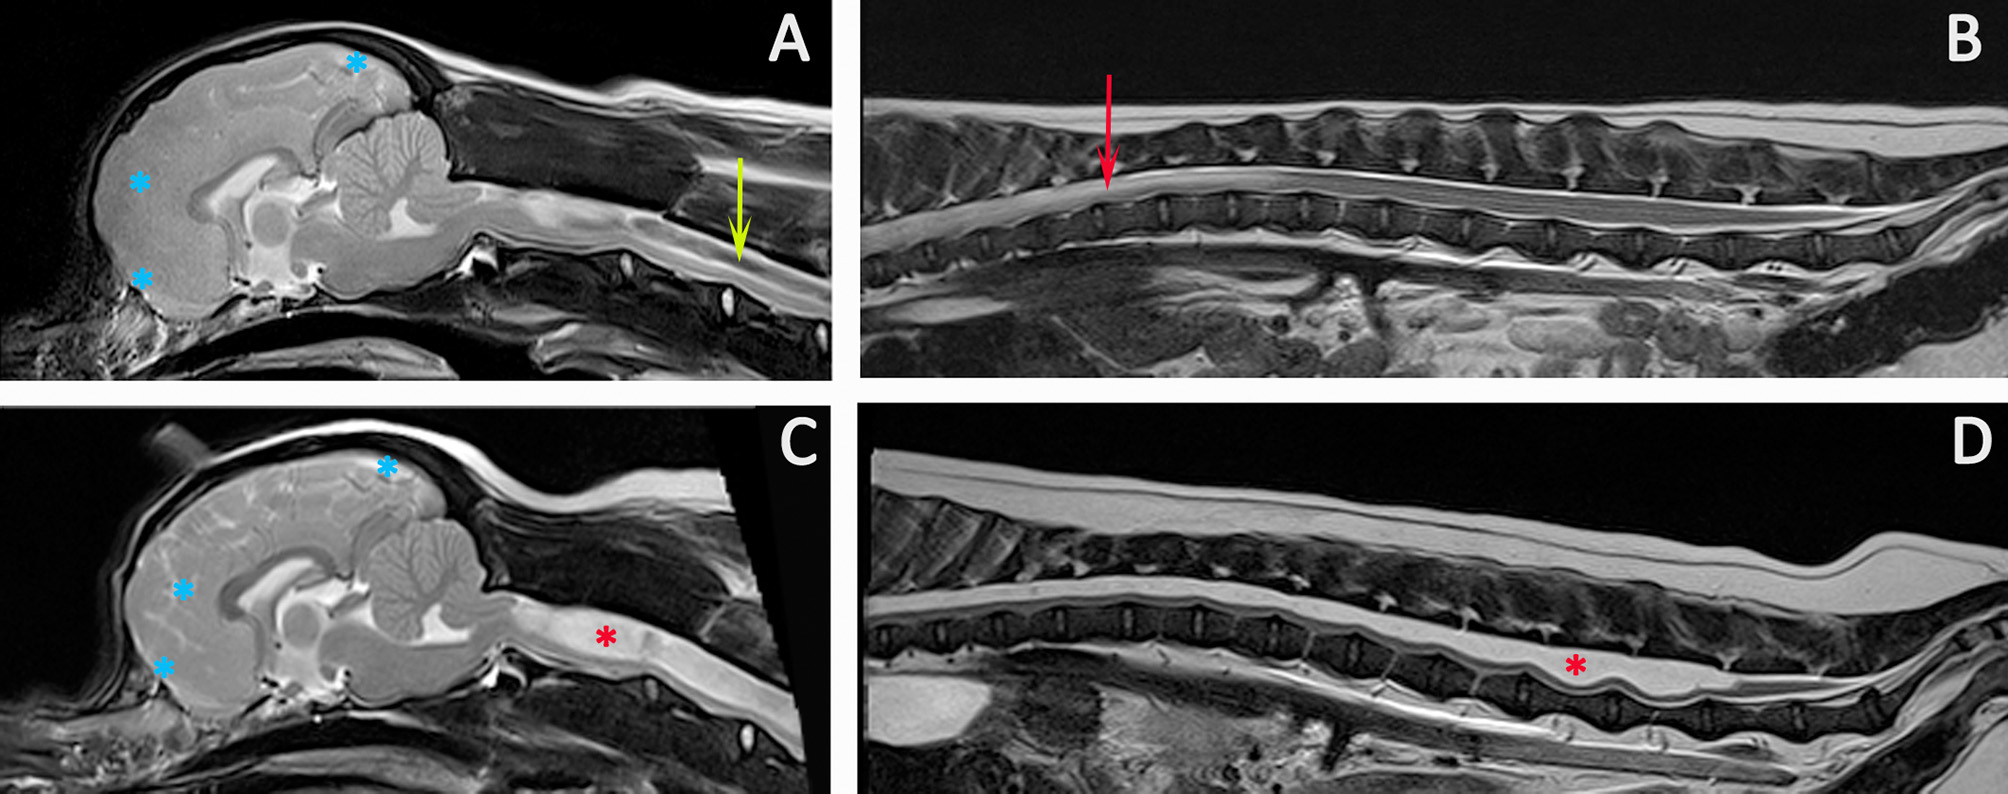

The diagnosis of SM implies a fluid filled cavity related to disturbance of CSF flow, spinal cord tethering or intramedullary tumor; it is not an appropriate description for myelomalacia or cystic lesions (14). SM can be asymptomatic (34) and when interpreting MRI, an assessment should be made as to whether the location and severity of the syrinx would account for the signs. Signs of an “active” and filling syrinx include fluid signal-void sign within the syrinx cavity indicating pulsatile or turbulent flow, hypothesized to be a cause of syrinx propagation (117) (Figure 9).

Figure 9

Progression of SM. Diagnostic Imaging of a female CKCS at 8 months old (A,B) and 3 years old (C,D). The CKCS was originally presented with signs of pain. When represented at 3 years of age, the signs of pain were no longer controlled by medication and she had mild thoracic limb hypermetria, tetraparesis, and pelvic limb ataxia. T2-weighted mid-sagittal MRI of the brain and cranial cervical spinal cord in a CM and SM affected CKCS (A) 8 months, (C) 3 years old T2-weighted mid-sagittal MRI of the vertebral column from T7 to Cy1 (B) 8 months, (D) 3 years old. (A,B) Imaging indicated risk of progressive SM with loss of the cranial subarachnoid space and effacement of the cranial sulci (blue asterisks), fluid signal-void sign within the syrinx suggesting pulsatile or turbulent flow (green arrow) and a pre-syrinx (oedema) and central canal dilatation in the caudal thoracic spinal cord (red arrow). (C,D) The syrinx has progressed to holocord SM (red asterisk). Although conclusions cannot be drawn without pressure measurements, it is interesting that MRI signs that can suggest elevated intra-cranial pressure (129) and fluid surging and pulsation within the syrinx (117) are diminished with an appreciably greater cranial subarachnoid space indicated by high signal CSF within the sulci (blue asterisks) and less fluid signal-void sign within the syrinx (Siemens Magnetom Symphony, A Tim System, 1.5 T, Erlangen, Germany).

In addition an active and filling syrinx is expansive within the spinal cord and generally has an asymmetrical shape on transverse images. By contrast a quiescent syrinx is centrally located, elliptical on sagittal images and symmetrical, usually circular on transverse images and results in little or no change to the outline of the spinal cord (87, 130). Symptomatic SM results in a myelopathy and therefore is suggested by sensory and motor signs that localize to the level of the spinal cord affected by the syrinx. However, gait disturbances may be surprisingly mild even with extensive SM. The dog in Figure 9 was presented with a mild pelvic limb ataxia, thoracic limb hypermetria and tetraparesis and was considered by the owner to have a normal exercise tolerance. If the clinical signs are disproportionate to the extent of the syrinx, other differentials should be explored for example degenerative myelopathy related to superoxide dismutase-1 mutation as a cause of pelvic limb paresis (48, 131). The maximum width of the syrinx on transverse images should be assessed; myelopathic signs in CKCS are associated with a syrinx transverse width of 4 mm or more whereas phantom scratching and cervicotorticollis/scoliosis are associated with extension of the syrinx into the superficial dorsal horn ipsilateral to the phantom scratching side and/or contralateral to the head tilt (48, 87). Phantom scratching is associated with extension to the superficial dorsal horn ipsilateral to the scratching side in the C3-C6 spinal cord segments (corresponding to C2-C5 vertebrae) (88). A guide is suggested in Figures 5, 8.